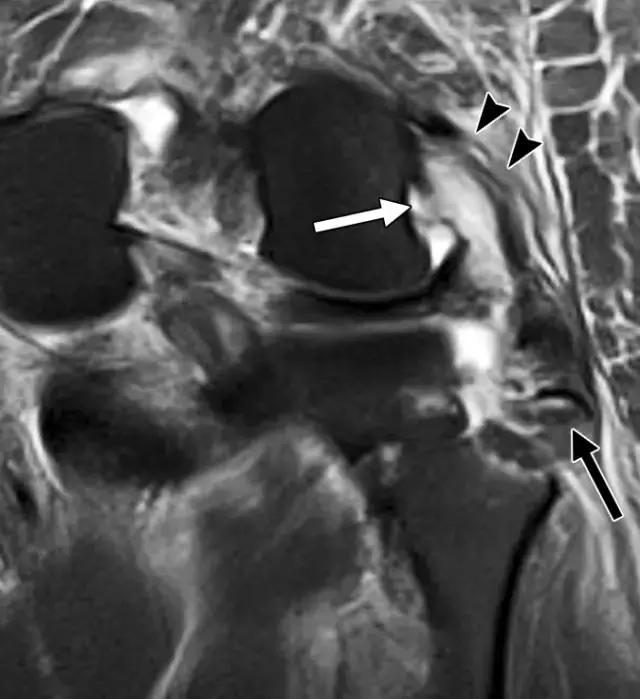

弓形骨折是近端腓骨的小撕裂性骨折。 在前后X光照片上最佳可视化,弓形标志是指通常位于腓骨头附近的腓骨腓骨片段(图10A)。 断裂与弓形复合体的一种或多种组分的撕裂有关,其可以包括以下结构:股二头肌;侧副韧带;腘肌肉和腱; 腘腓骨和腘半月板韧带;和斜腘,弓形和腓肠豆腓侧韧带。 骨折不仅表现为外侧膝盖的临床重要的软组织损伤,而且通常与其他损伤有关。 在一项研究中,72%的弓形骨折患者也有ACL损伤,67%的患者出现PCL撕裂(图10B)。

图10A -26岁的女子与弓形标志。膝关节前后X线照片显示位移水平方向的腓骨头骨折(箭头)和外侧关节隔室的加宽。

图10B,冠状脂肪抑制的T2加权MR图像显示撕脱骨折(黑色箭头)和广泛的软组织水肿和外侧副韧带(箭头)和腘腱(白色箭头)的撕裂。

后外侧角损伤的临床诊断可能是具有挑战性的,因为身体检查中的发现通常是轻微的。 因此,成像在这些患者的治疗中起关键作用,因为在ACL或PCL重建时未能识别后外侧角部损伤,可能导致早期移植失败。